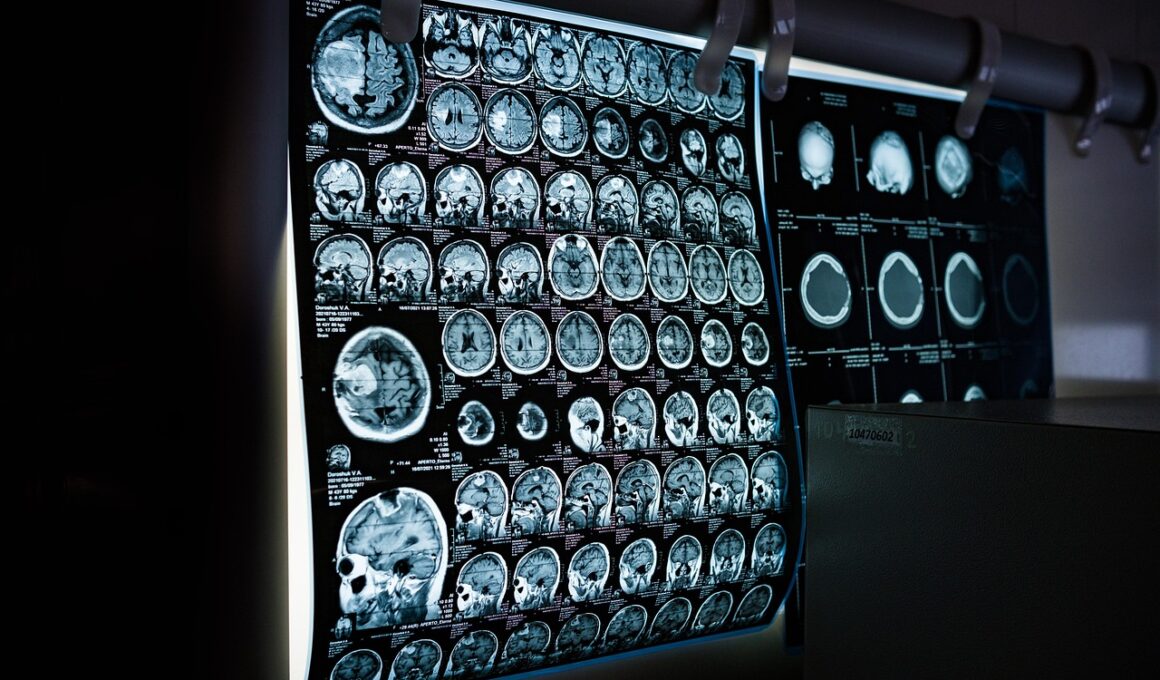

Diagnostic imaging serves as a foundational tool in sports medicine, particularly for shoulder injuries. It allows for meticulous evaluation of injuries that may not be apparent through physical examination alone. Various imaging modalities, including MRI, CT, and ultrasound, each have unique benefits and limitations in assessing shoulder conditions. MRI is particularly effective due to its superior soft tissue contrast, revealing details of rotator cuff injuries, labral tears, and other critical findings. In contrast, ultrasound offers a dynamic assessment, allowing real-time visualization during shoulder movement. Consequently, it can be particularly effective for examining dynamic instability and guiding therapeutic injections. Additionally, X-rays remain a primary tool for evaluating bony anatomy, identifying fractures, and assessing joint alignment. Selecting the appropriate imaging technique depends on the clinical presentation, the specific injury suspected, and the athlete’s activity level. Moreover, several factors influence the choice of imaging, such as cost, accessibility, and the physician’s experience with different modalities. Ultimately, the goal is to provide a comprehensive diagnostic picture that informs effective treatment strategies.

There are three primary imaging techniques used to evaluate shoulder injuries in athletes: X-rays, MRIs, and Ultrasound. Each technique serves a specific purpose and offers different advantages. X-rays, the most commonly used, provide crucial information about bone structure, enabling quick assessment of fractures, dislocations, and bone alignment. However, they offer limited insight into soft tissue injuries. MRI has become a preferred method for allowing detailed visualization of muscles, tendons, ligaments, and cartilage. This imaging allows accurate diagnosis of various conditions, including rotator cuff pathology and labral tears. Ultrasound, on the other hand, is advantageous due to its portability and ability to assess dynamic movement. It is particularly useful in guiding injections for therapeutic purposes and can help pinpoint issues dynamically as they occur. Each imaging modality has specific indications based on the type and severity of the shoulder injury. Therefore, a comprehensive understanding of these imaging modalities is crucial for clinicians and trainers involved in athlete care. This understanding ultimately leads to effective injury management and optimal recovery outcomes.